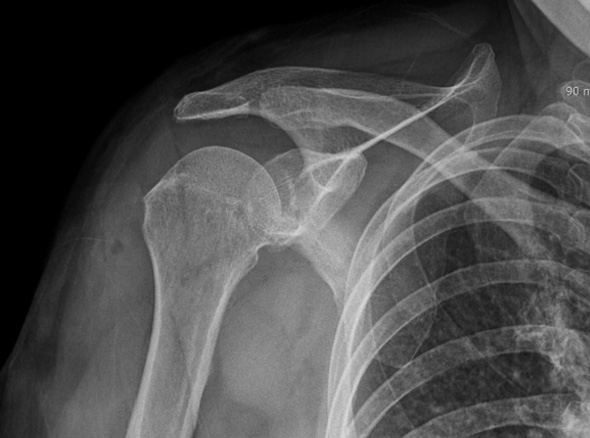

정확한 진단을 통하여 무조건 비수술적 치료, 무조건 수술적 치료가 아니라

환자의 상태에 맞는 최선의 치료를 선택할 수 있게 합니다.

관절 내시경을 통한

견봉 성형술

관절 내시경을 통하여

힘줄 손상을 유발하는 견봉하 골극을 제거합니다.